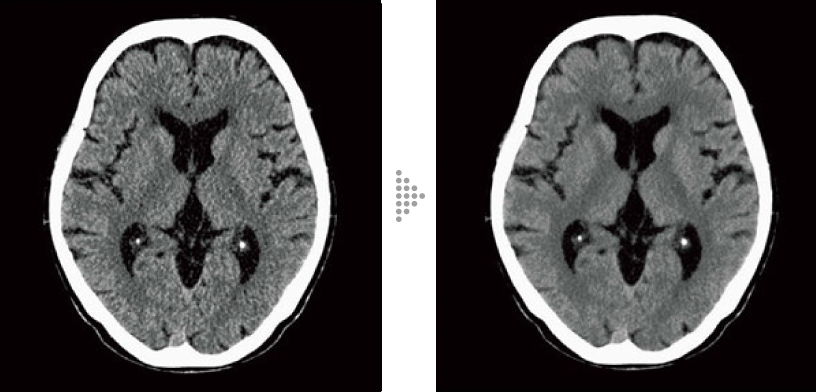

FBP(izquierda)

Intelli IPV(derecha)